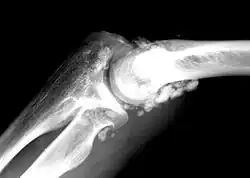

Die Synoviale Chondromatose ist eine seltene Erkrankung der Synovialis großer Gelenke. Es handelt sich um eine knorpelbildende Metaplasie (Chondromatose). Die ersten Kasuistiken stammen von Paul Friedrich Reichel, Melvin Starkey Henderson (1918) und Hugh Toland Jones (1924).[1][2][3] Die Ursache ist der Erkrankung ist unbekannt.

„Häufig“ befallen sind Knie-, Hüft-, Schulter- und Ellbogengelenk.[6] Auch das Kiefergelenk kann betroffen sein.[7][8]

Die synoviale Chondromatose ist eine radiologische Blickdiagnose. Als gefürchtete Komplikation ist die Entstehung eines sekundären Chondrosarkoms zu sehen.[9][10] In einer größeren Studie mit 53 Fällen in 30 Jahren wurden drei Chondrosarkome diagnostiziert.[4]